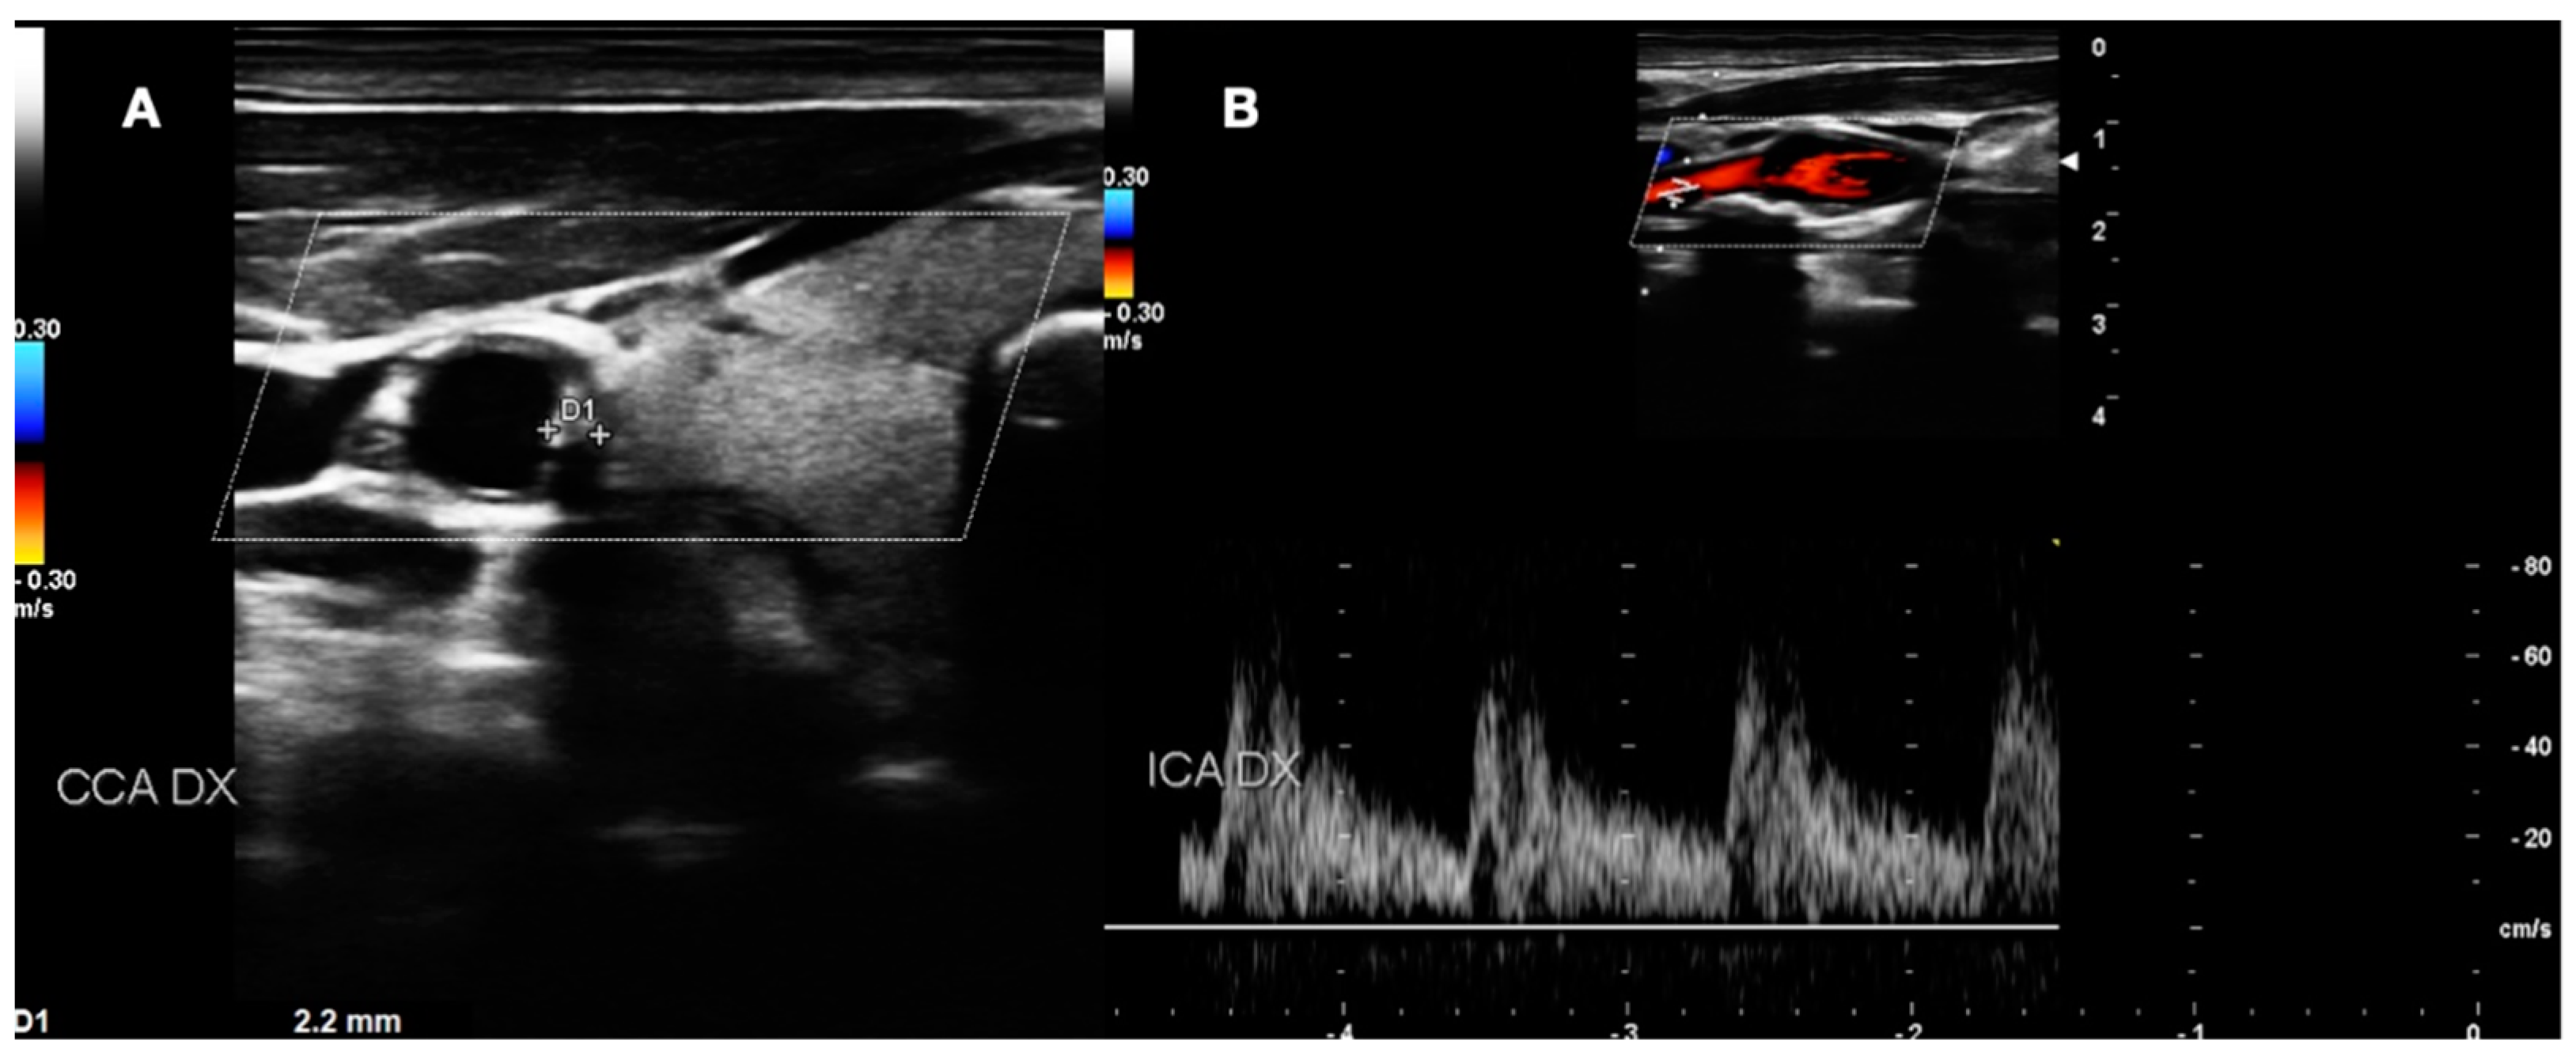

- LOW GRADE and MEDIUM GRADE: Patients presenting a carotid plaque under 30% of stenosis. In these cases, a cardiology evaluation was added, and a clinical path of the main arterial districts (aorta and peripheral arteries) was concluded by DUS (Figure 5 and Figure 6).

Figure 5. DUS images showing plaque in CCA—LOW GRADE (A), and its relative flow (B).

Figure 6. DUS images showing plaque in CCA—MEDIUM GRADE (A), and its relative flow (B).

- HIGH GRADE: Patients presenting a carotid plaque over 30% and further divided in the first step (under 50% of stenosis), the second step (stenosis between 50% and 70%), the third step (above 70%). All patients in this group underwent cardiologic assessment, with echocardiography, electrocardiogram, and DUS of peripheral arteries (Figure 7).

Figure 7. DUS images showing plaque in CCA—HIGH GRADE (A), and its relative flow (B).